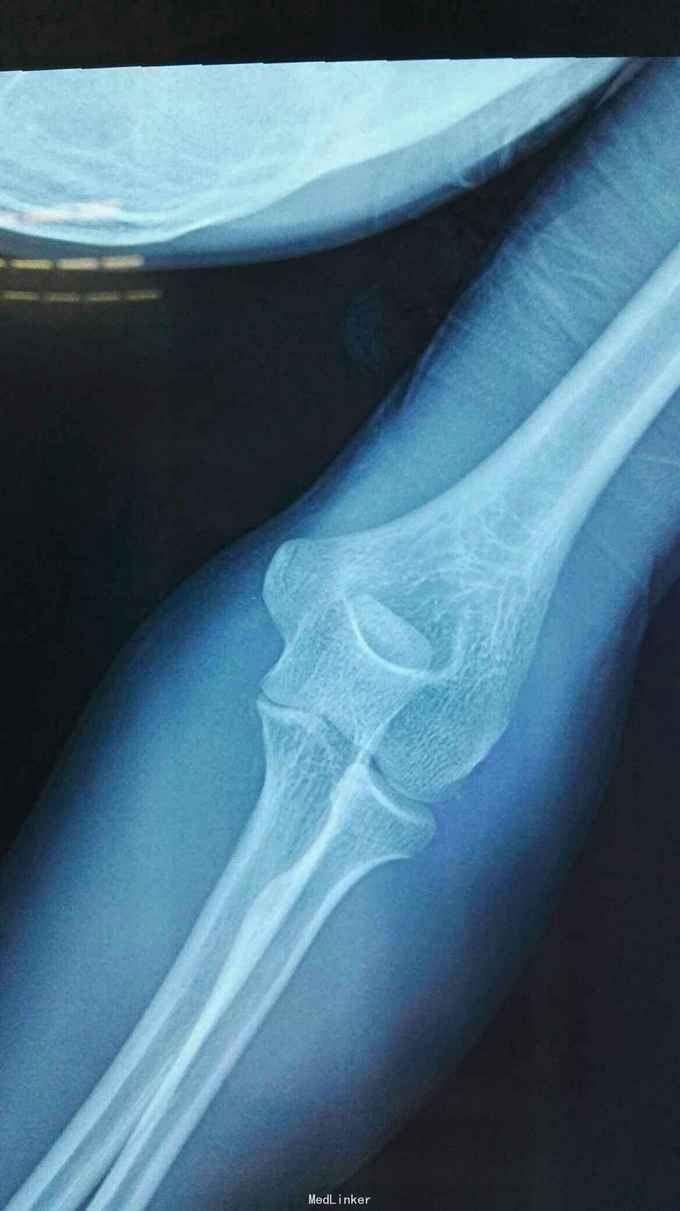

右肘跌伤疼痛伴不能活动1天。 患者,男,14岁,1天前跌倒,感右肘部剧痛,不能活动,急送当地医院拍片示:右肘关节脱位,尺骨冠狀突骨折,右桡骨小头骨折,行手法复位,今来我院就诊。

查体:右肘关节高度肿胀,触痛,活动功能障碍手指末端感觉血运正常。 辅查:x线,CT:右肘关节脱位,右尺骨冠突骨折,右桡骨小头骨折

诊断:右肘恐怖三联症。 治疗:伤后第6天在全麻下行右肘恐怖三联症切开复位内固定术,术中先取肘外侧弧形切口,显露桡骨头,用2枚埋头螺钉固定桡骨头,见右肘外侧副韧带尺侧束断裂,用锚钉固定外侧副韧带。取右肘内侧弧形口,显露冠状突,见冠状突骨折块很小,移位较远,复位,2枚螺钉固定,内侧副韧带前束断裂,修补,术后石膏因定。